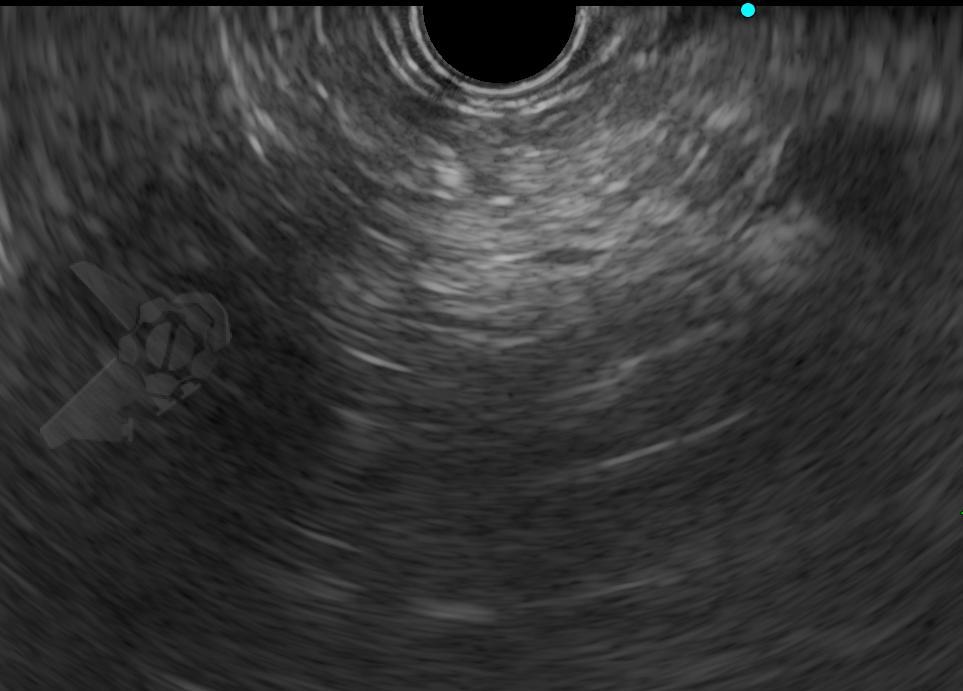

El diagnóstico mediante EUS se basó en la presencia de imágenes pancreáticas hiperecoicas difusas o discontinuas, con bordes poco definidos y dificultad para caracterizar el conducto pancreático principal, en lugar del aspecto habitual bien definido de «sal y pimienta» (véanse las imágenes ilustrativas en el artículo).

Imágenes ilustrativas: